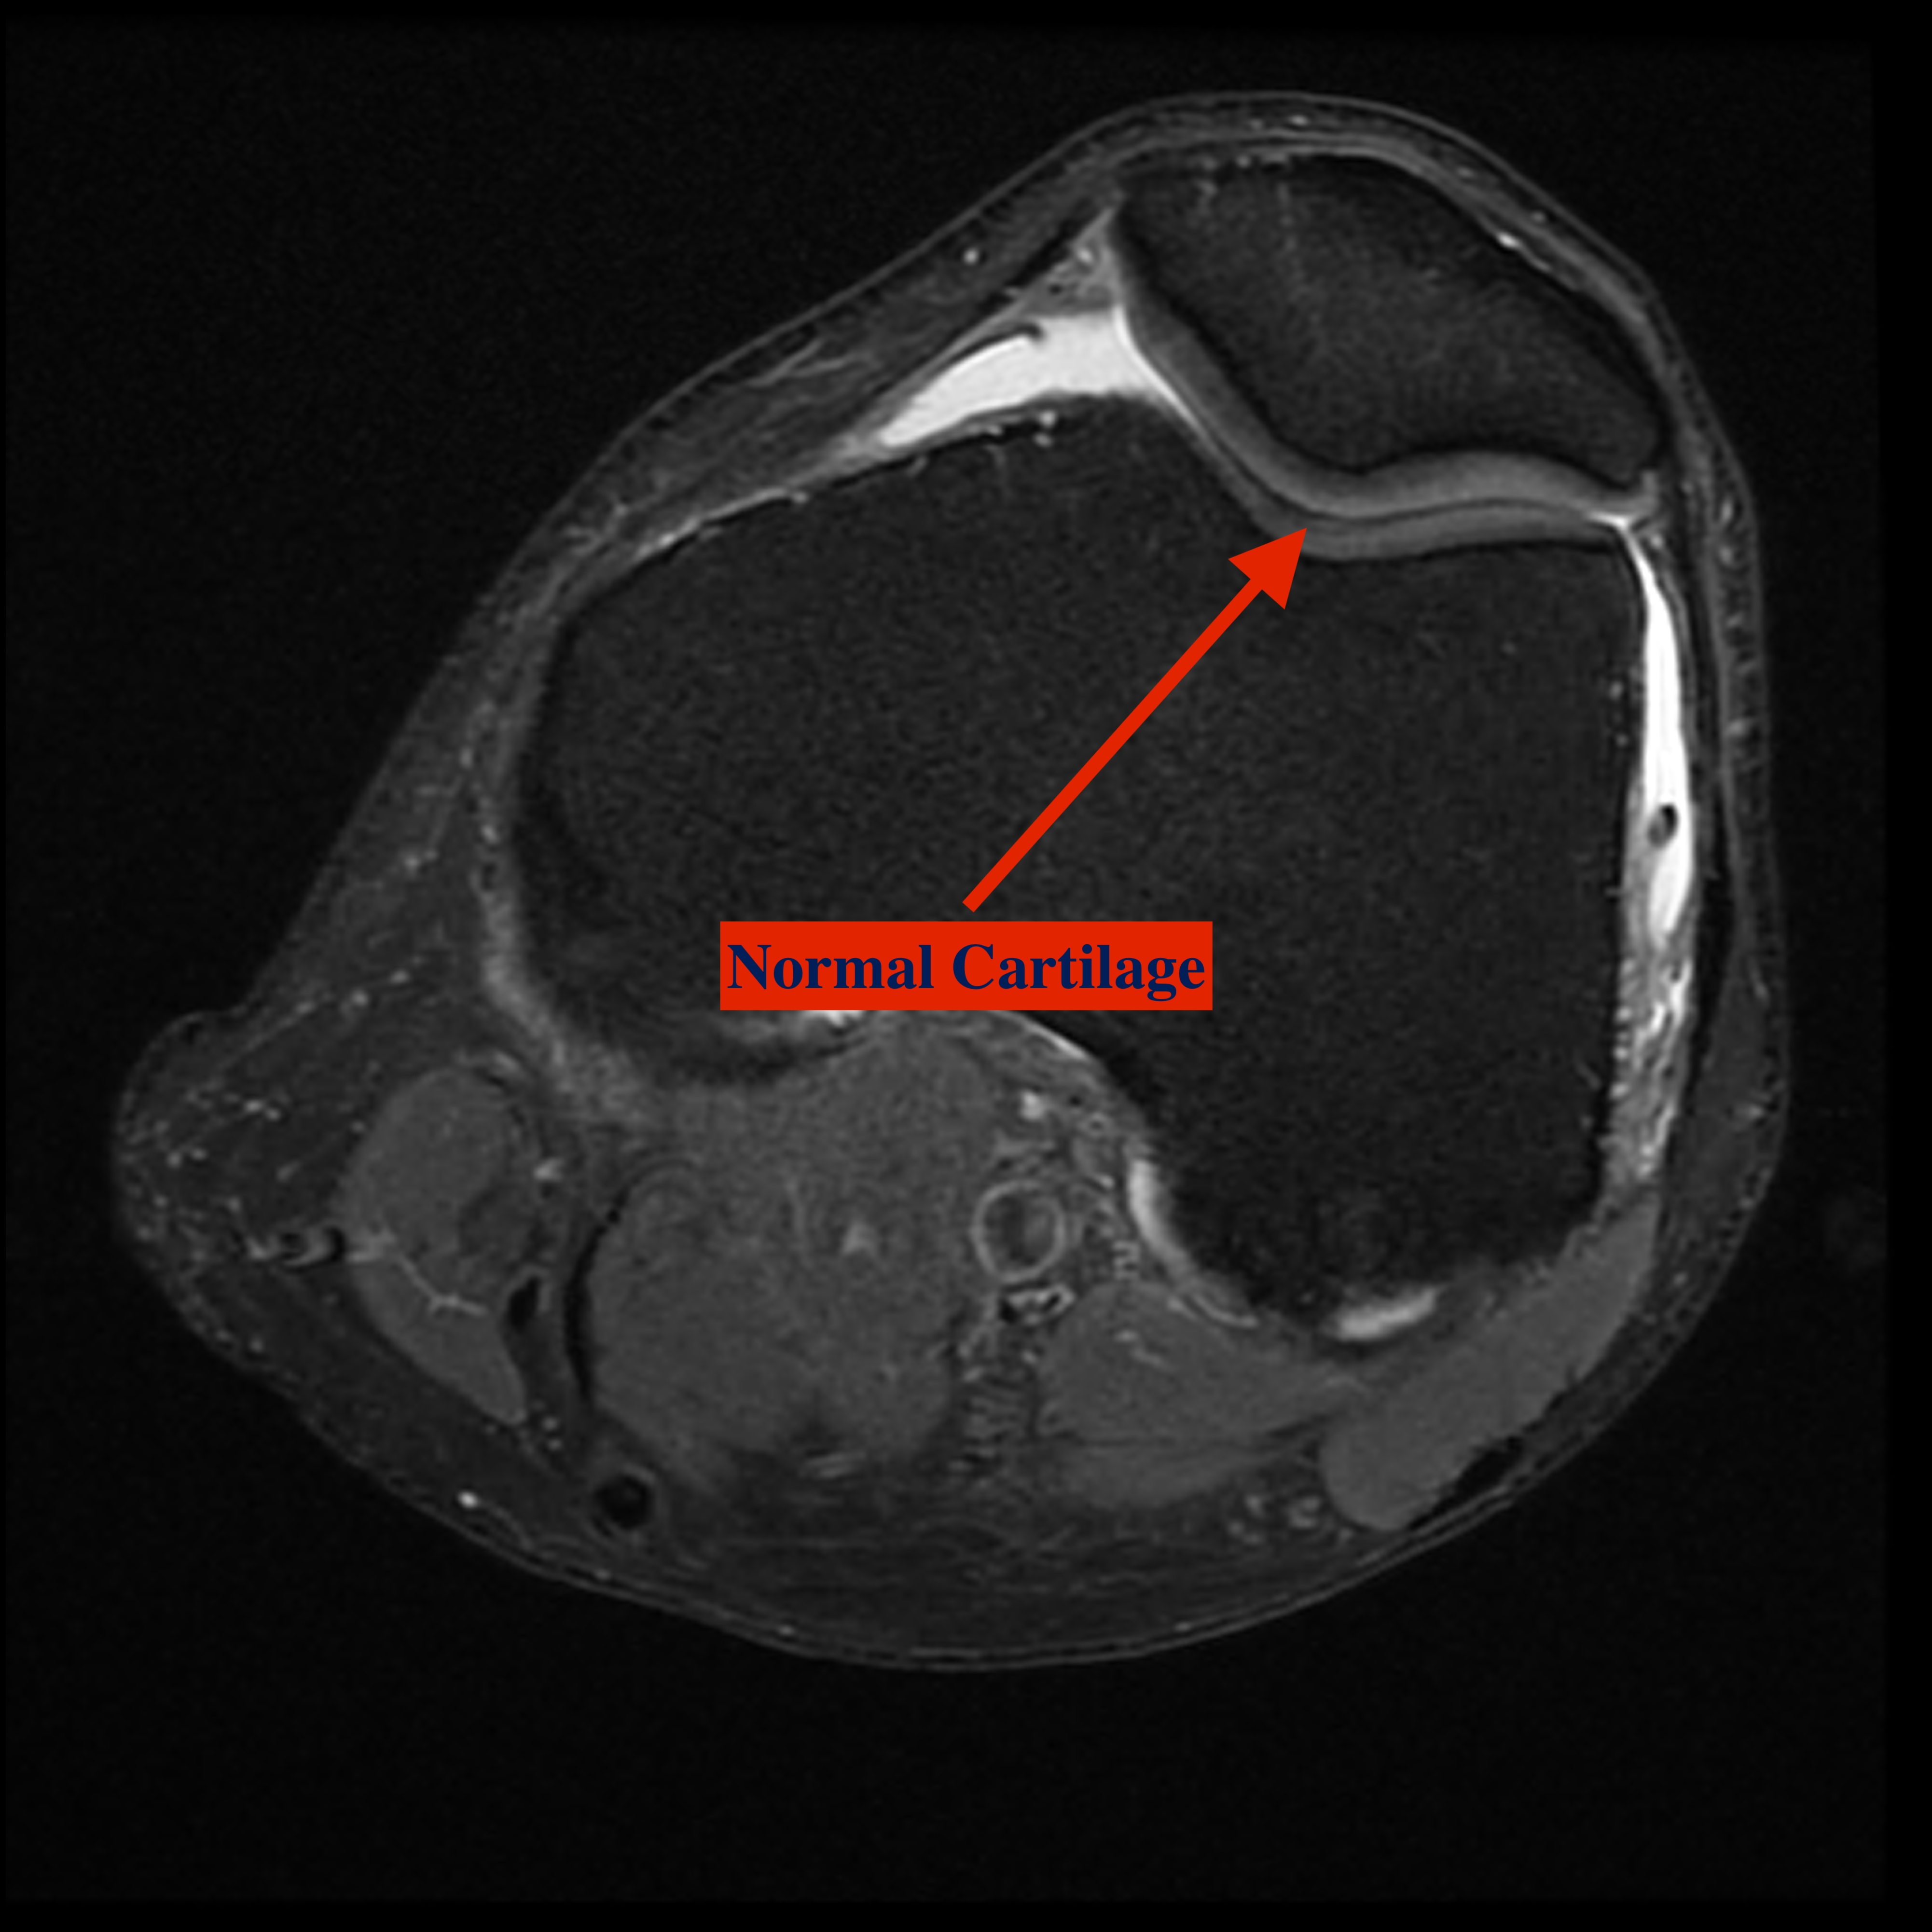

Patellofemoral arthritis occurs when the articular cartilage along the trochlear groove and on the underside of the patella wears down and becomes inflamed. When cartilage wears away, it becomes frayed and, when the wear is severe, the underlying bone may become exposed. Moving the bones along this rough surface may be painful.

Cartilage grafting. Normal healthy cartilage tissue may be taken from another part of the knee or from a tissue bank to fill a hole in the articular cartilage. This procedure is typically considered only for younger patients who have small areas of cartilage damage.